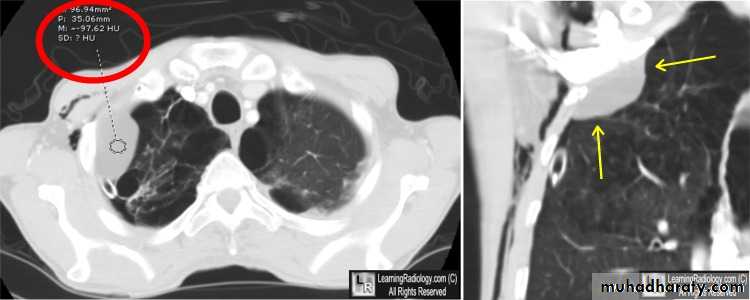

Diseases of the pleura• 1-Spontaneous pneumothorax

Is the accumulation of air inside the pleural cavity , occurring without any known etiology .More in males ,more on the right side .It can be bilateral

• Causes 1- Ruptured pulmonary bleb.2-Ruptured of a cystic defect in the pleura.3-Teared visceral pleura 4-No cause can be demonstrated in (15-20%).Complications:-1-pleural effusion2-empyema 3-tension pneumothorax which leads to mediastinal shift &circulatory collapse.4-Respiratory failure in elderly patient with COAD .